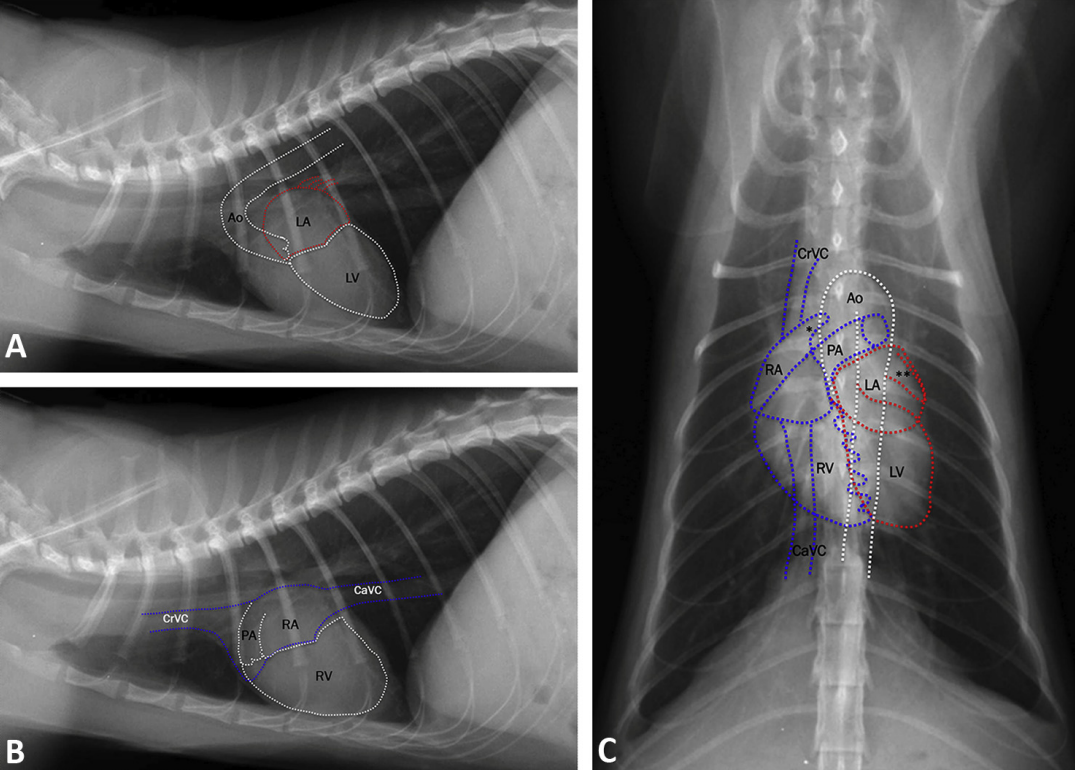

canine and feline VHS : 개와 고양이의 심장 크기평가

In cat : 7.3-8.1